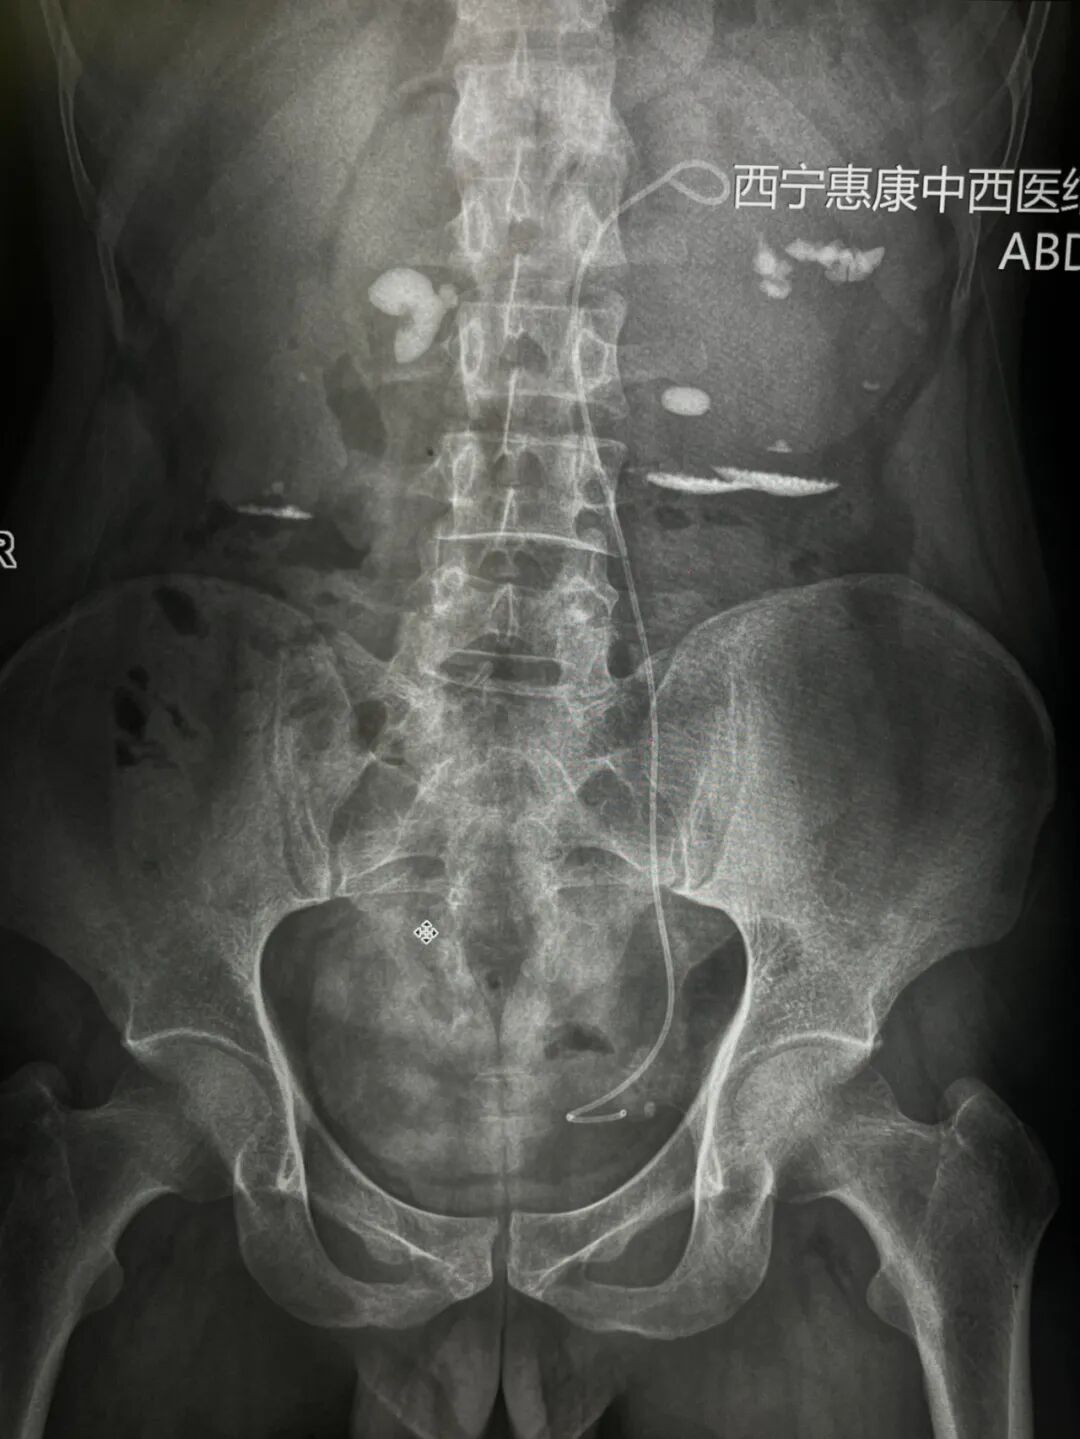

该患者2个月前曾接受左侧输尿管支架管置入术,近期因身体不适前往我院就诊,入院诊断:肾输尿管结石伴有积水和感染(左侧),肾积水伴肾结石(右侧),肾功能不全,入院后组织科内会诊及术前检查,考虑输尿管上段结石,体积大,且与输尿管粘膜黏连严重,俗称“肉包石”,且合并左肾多发结石,综合考虑经皮肾微造瘘碎石取石术。

针对患者的病情,我院泌尿外科立即组织多学科协作团队开展病例讨论。团队结合患者既往手术史、影像学检查结果及身体整体状况,进行多维度评估后认为,需通过联合手术清除结石、改善尿路通畅度并控制感染,最终确定联合手术方案的治疗方案,左肾微创碎石取石及右肾造瘘术。术前,分肾功能测定,右肾仅剩5%;ct片显示,右肾皮质尚有一定厚度,我院医疗团队判定右肾仍有恢复的可能,为尽可能保留右肾参与功能,于是进行了右肾穿刺造瘘。3个月以后进行复查,进行再次的分肾功能测定之后了解右肾功能恢复状况再进行下一步的治疗方案。

对于左肾,我院医疗团队决定保留肾造瘘管引流,有利于其变形的肾盂结构恢复,待左肾引流一段时间之后,从原造瘘口清楚残余结石。手术过程中,诊疗团队严格遵循手术规范,主刀医生凭借多年临床经验与规范操作,在经皮肾镜辅助下逐步击碎并取出左肾及输尿管内的结石,从根源上解决梗阻问题;同时更换原有输尿管支架管,确保术后尿液能够顺利引流,避免再次梗阻;右肾造瘘术的实施则进一步缓解了肾脏压力,为控制感染、保护肾功能提供保障。整个手术历时数小时,各环节衔接有序,最终顺利完成。